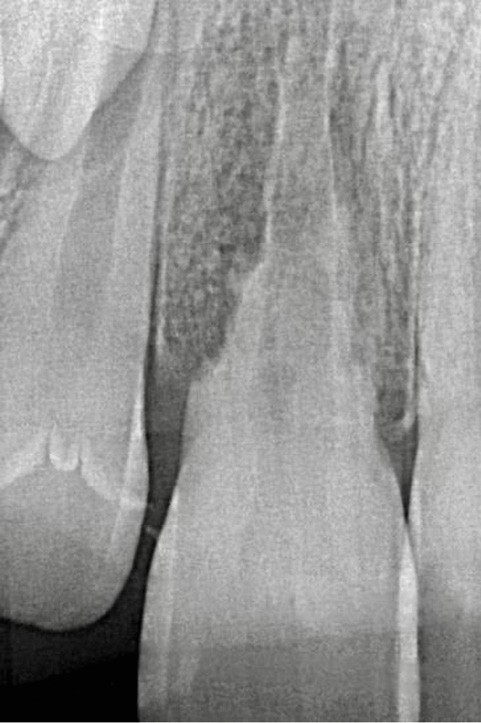

Les résorptions radiculaires inflammatoires externes surviennent après un traumatisme sévère comme une avulsion (fig. 1) ou une luxation [3], où la couche protectrice de précément et le parodonte sont altérés. Ces traumatismes peuvent provoquer une compression tissulaire au niveau du ligament parodontal, induisant des lésions vasculaires, une hypoxie et une perte d’intégrité du cément. Si la dent est restée vivante alors, un processus de réparation se met en place avec l’apposition d’un nouveau cément et d’une nouvelle attache. En revanche, si la dent venait à se nécroser, alors les stimuli pro inflammatoires résultant de l’activité des bactéries au sein du canal vont diffuser à travers les tubuli dentinaires et rejoindre les zones de résorption externe, et ainsi vont aggraver le processus résorptif qui est déjà actif [4].

Les RREI se manifestent par des signes de parodontite apicale : douleur, gonflement, sensibilité à la percussion ou à la palpation, fistule ou dyschromie de la couronne. En général, la dent affectée présente une réponse négative aux tests de sensibilité pulpaire [5]. L’examen radiographique montre des zones radioclaires irrégulières (aspect déchiqueté) autour de la racine lorsque la résorption est active. Le canal radiculaire reste visible et bien identifiable. Dans les cas avancés de résorption, la racine peut être complètement résorbée. Un examen 3D (CBCT : Cone Beam Computed Tomography) est recommandé pour aider au diagnostic et à la prise en charge de la RREI qui, cliniquement, semble traitable [6].